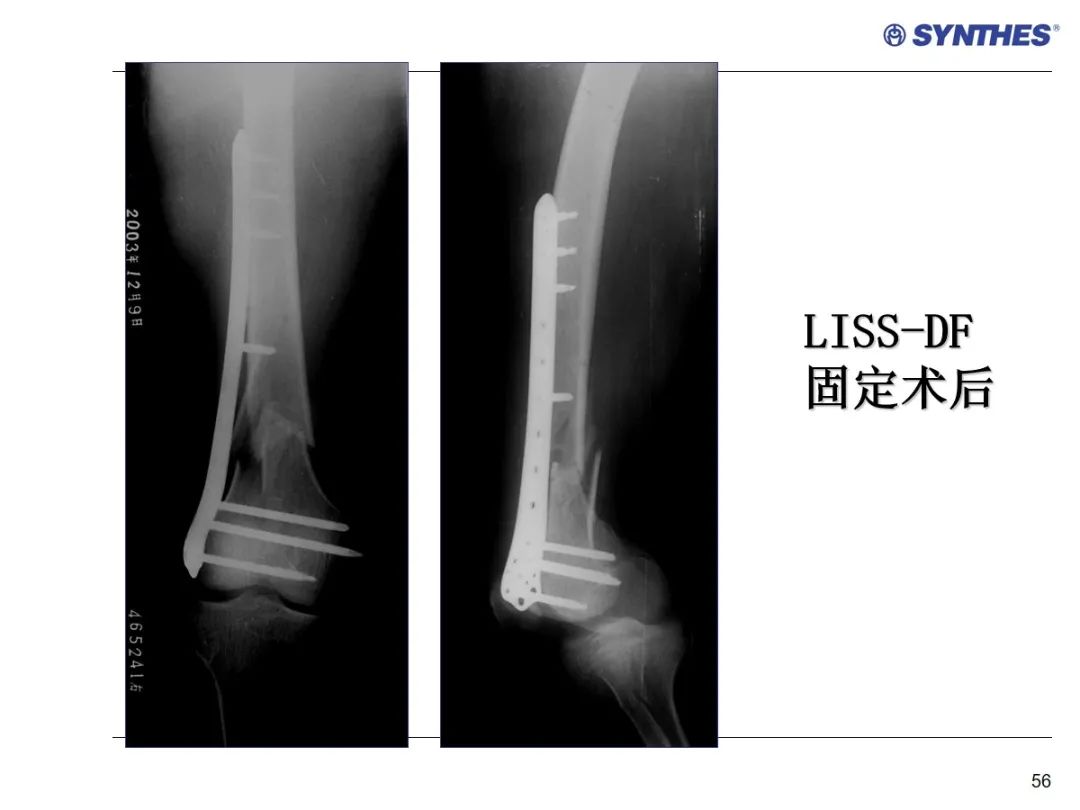

LISS微创固定系统应用技巧,原来如此简单!